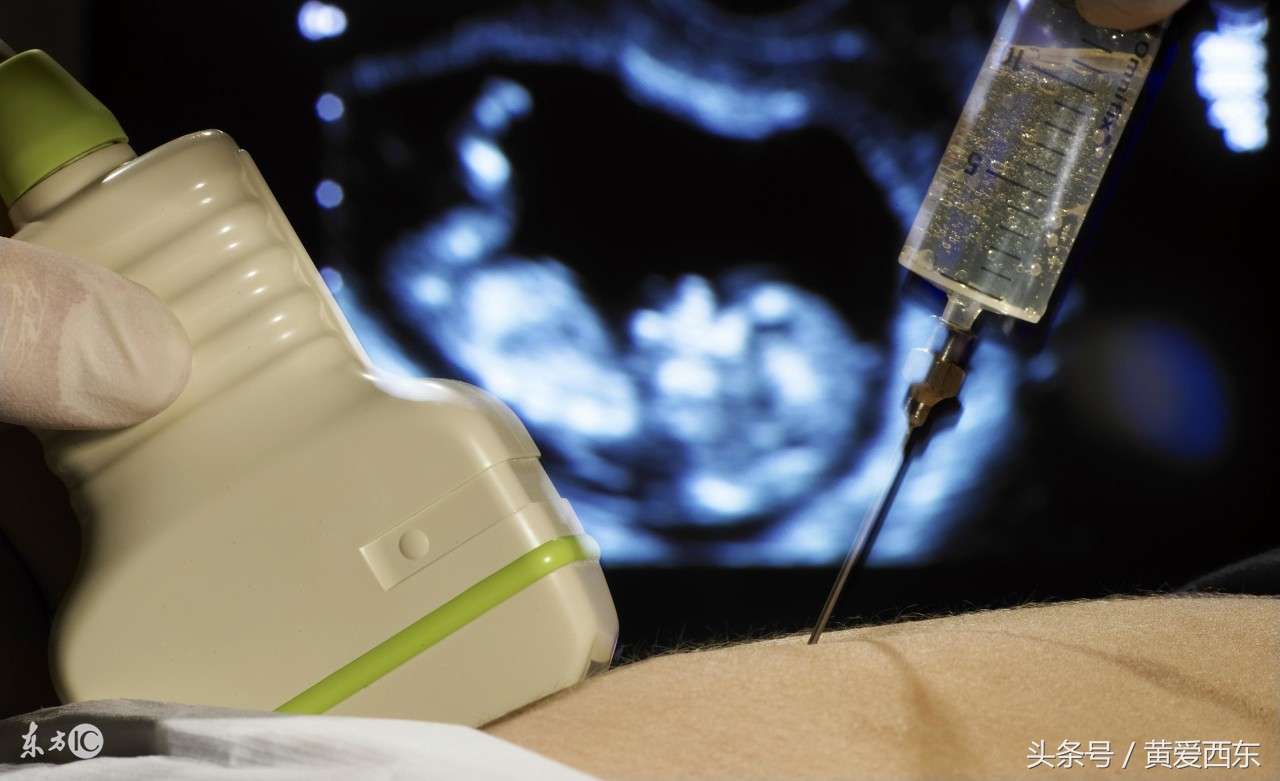

除了自然生产时的剧烈疼痛,是的,还有剖腹产,但是,你知道吗?剖宫产的孕妇刀口的疼痛完全不比生产的疼痛差啊!生完孩子后的0到3、4天内,麻醉过去了,就是生生的肉痛,刀口痛,生不如死!生无可恋!